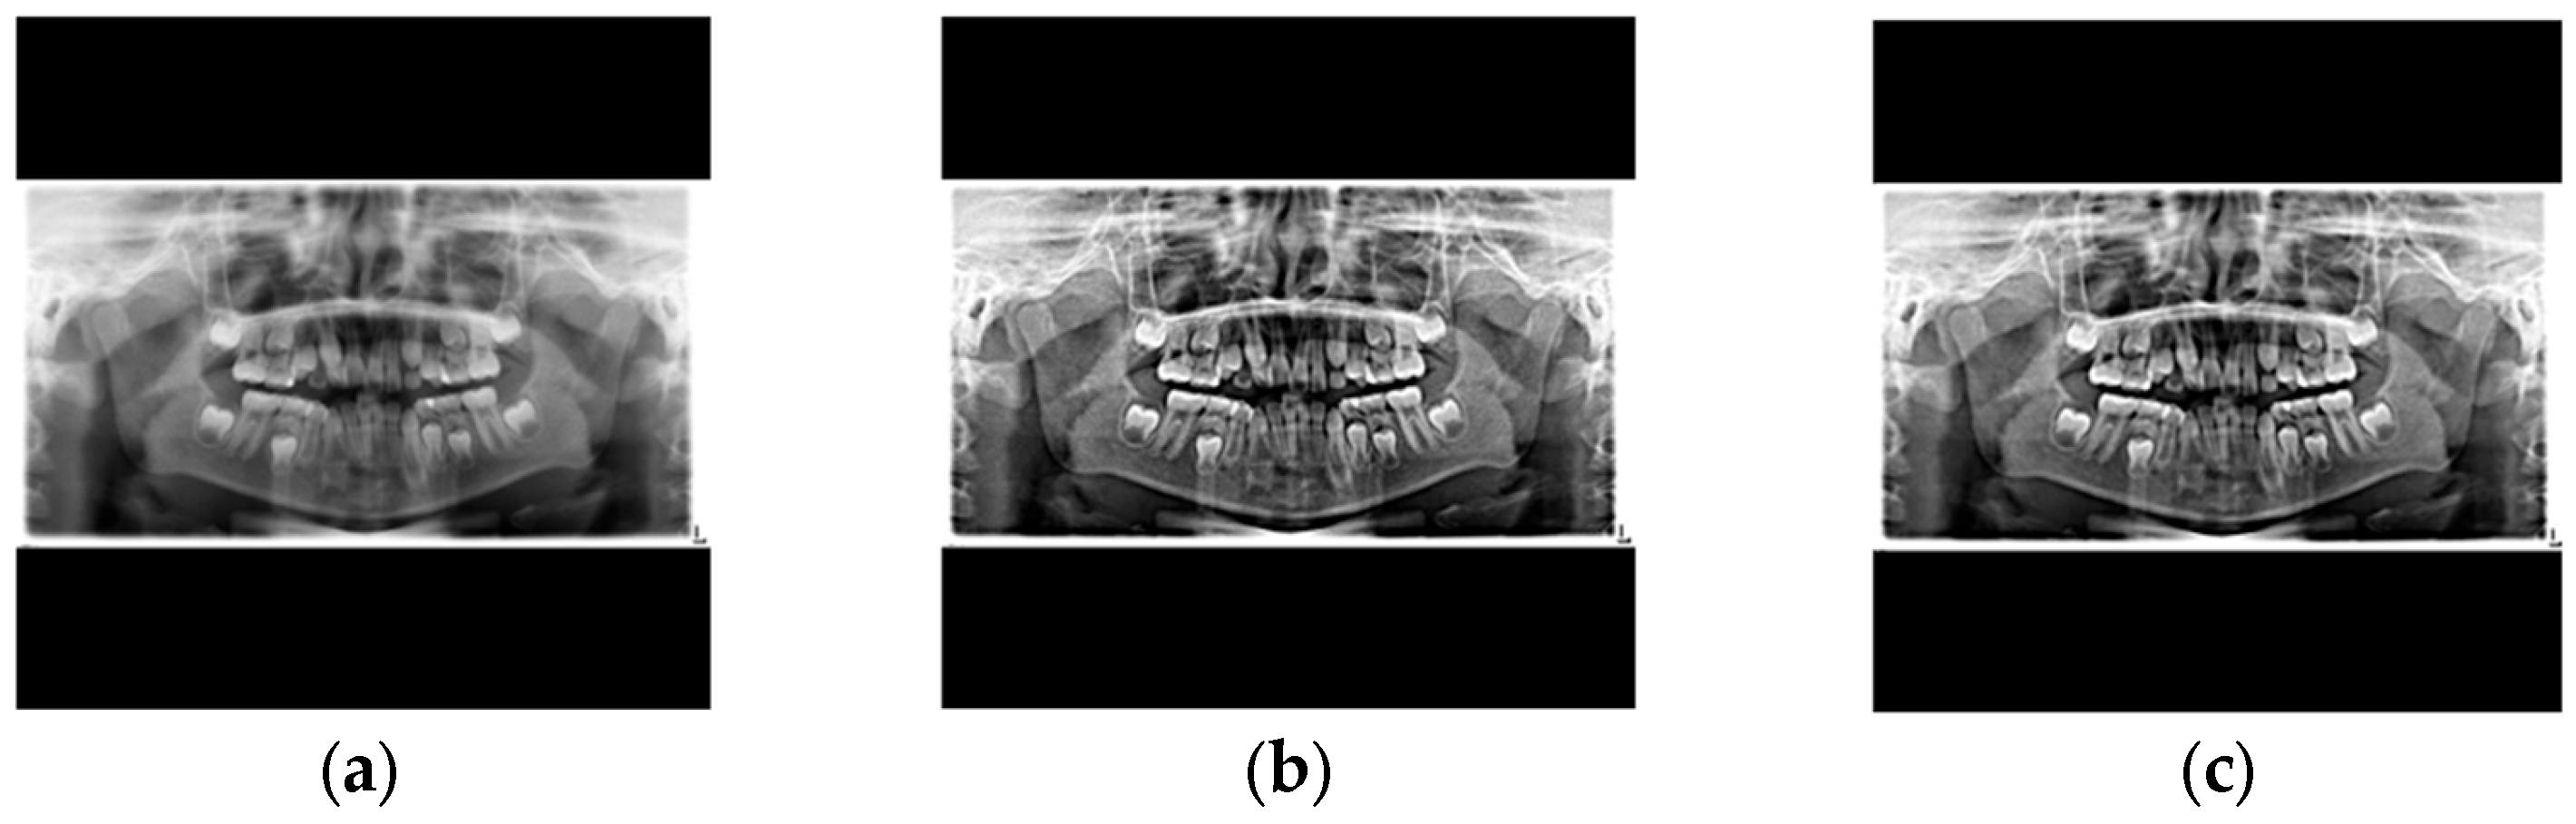

| Cutting Black Borders + Padding | Sharpening + Median Filtering | |

|---|---|---|

| Precision ↑ | 95.07 | 98.16 |

| Recall ↑ | 97.86 | 98.44 |

| mAP50 ↑ | 98.22 | 98.48 |

| mAP50~95 ↑ | 70.18 | 72.94 |

| F1-score ↑ | 96.44 | 98.30 |

| Image | ![]() | ![]() |